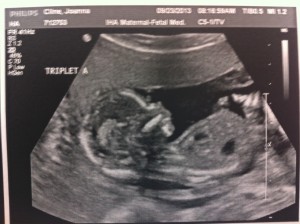

Hello!! I’m 16 weeks today and it was the BIG appointment where we learned the sex of the fetuses!!

Baby A – is a BOY!

Baby B – is a GIRL!

Baby C – is a BOY!

A is 170 grams, B is 175 grams and C is 178 grams so they’re all measuring well. Grow, grow, grow!